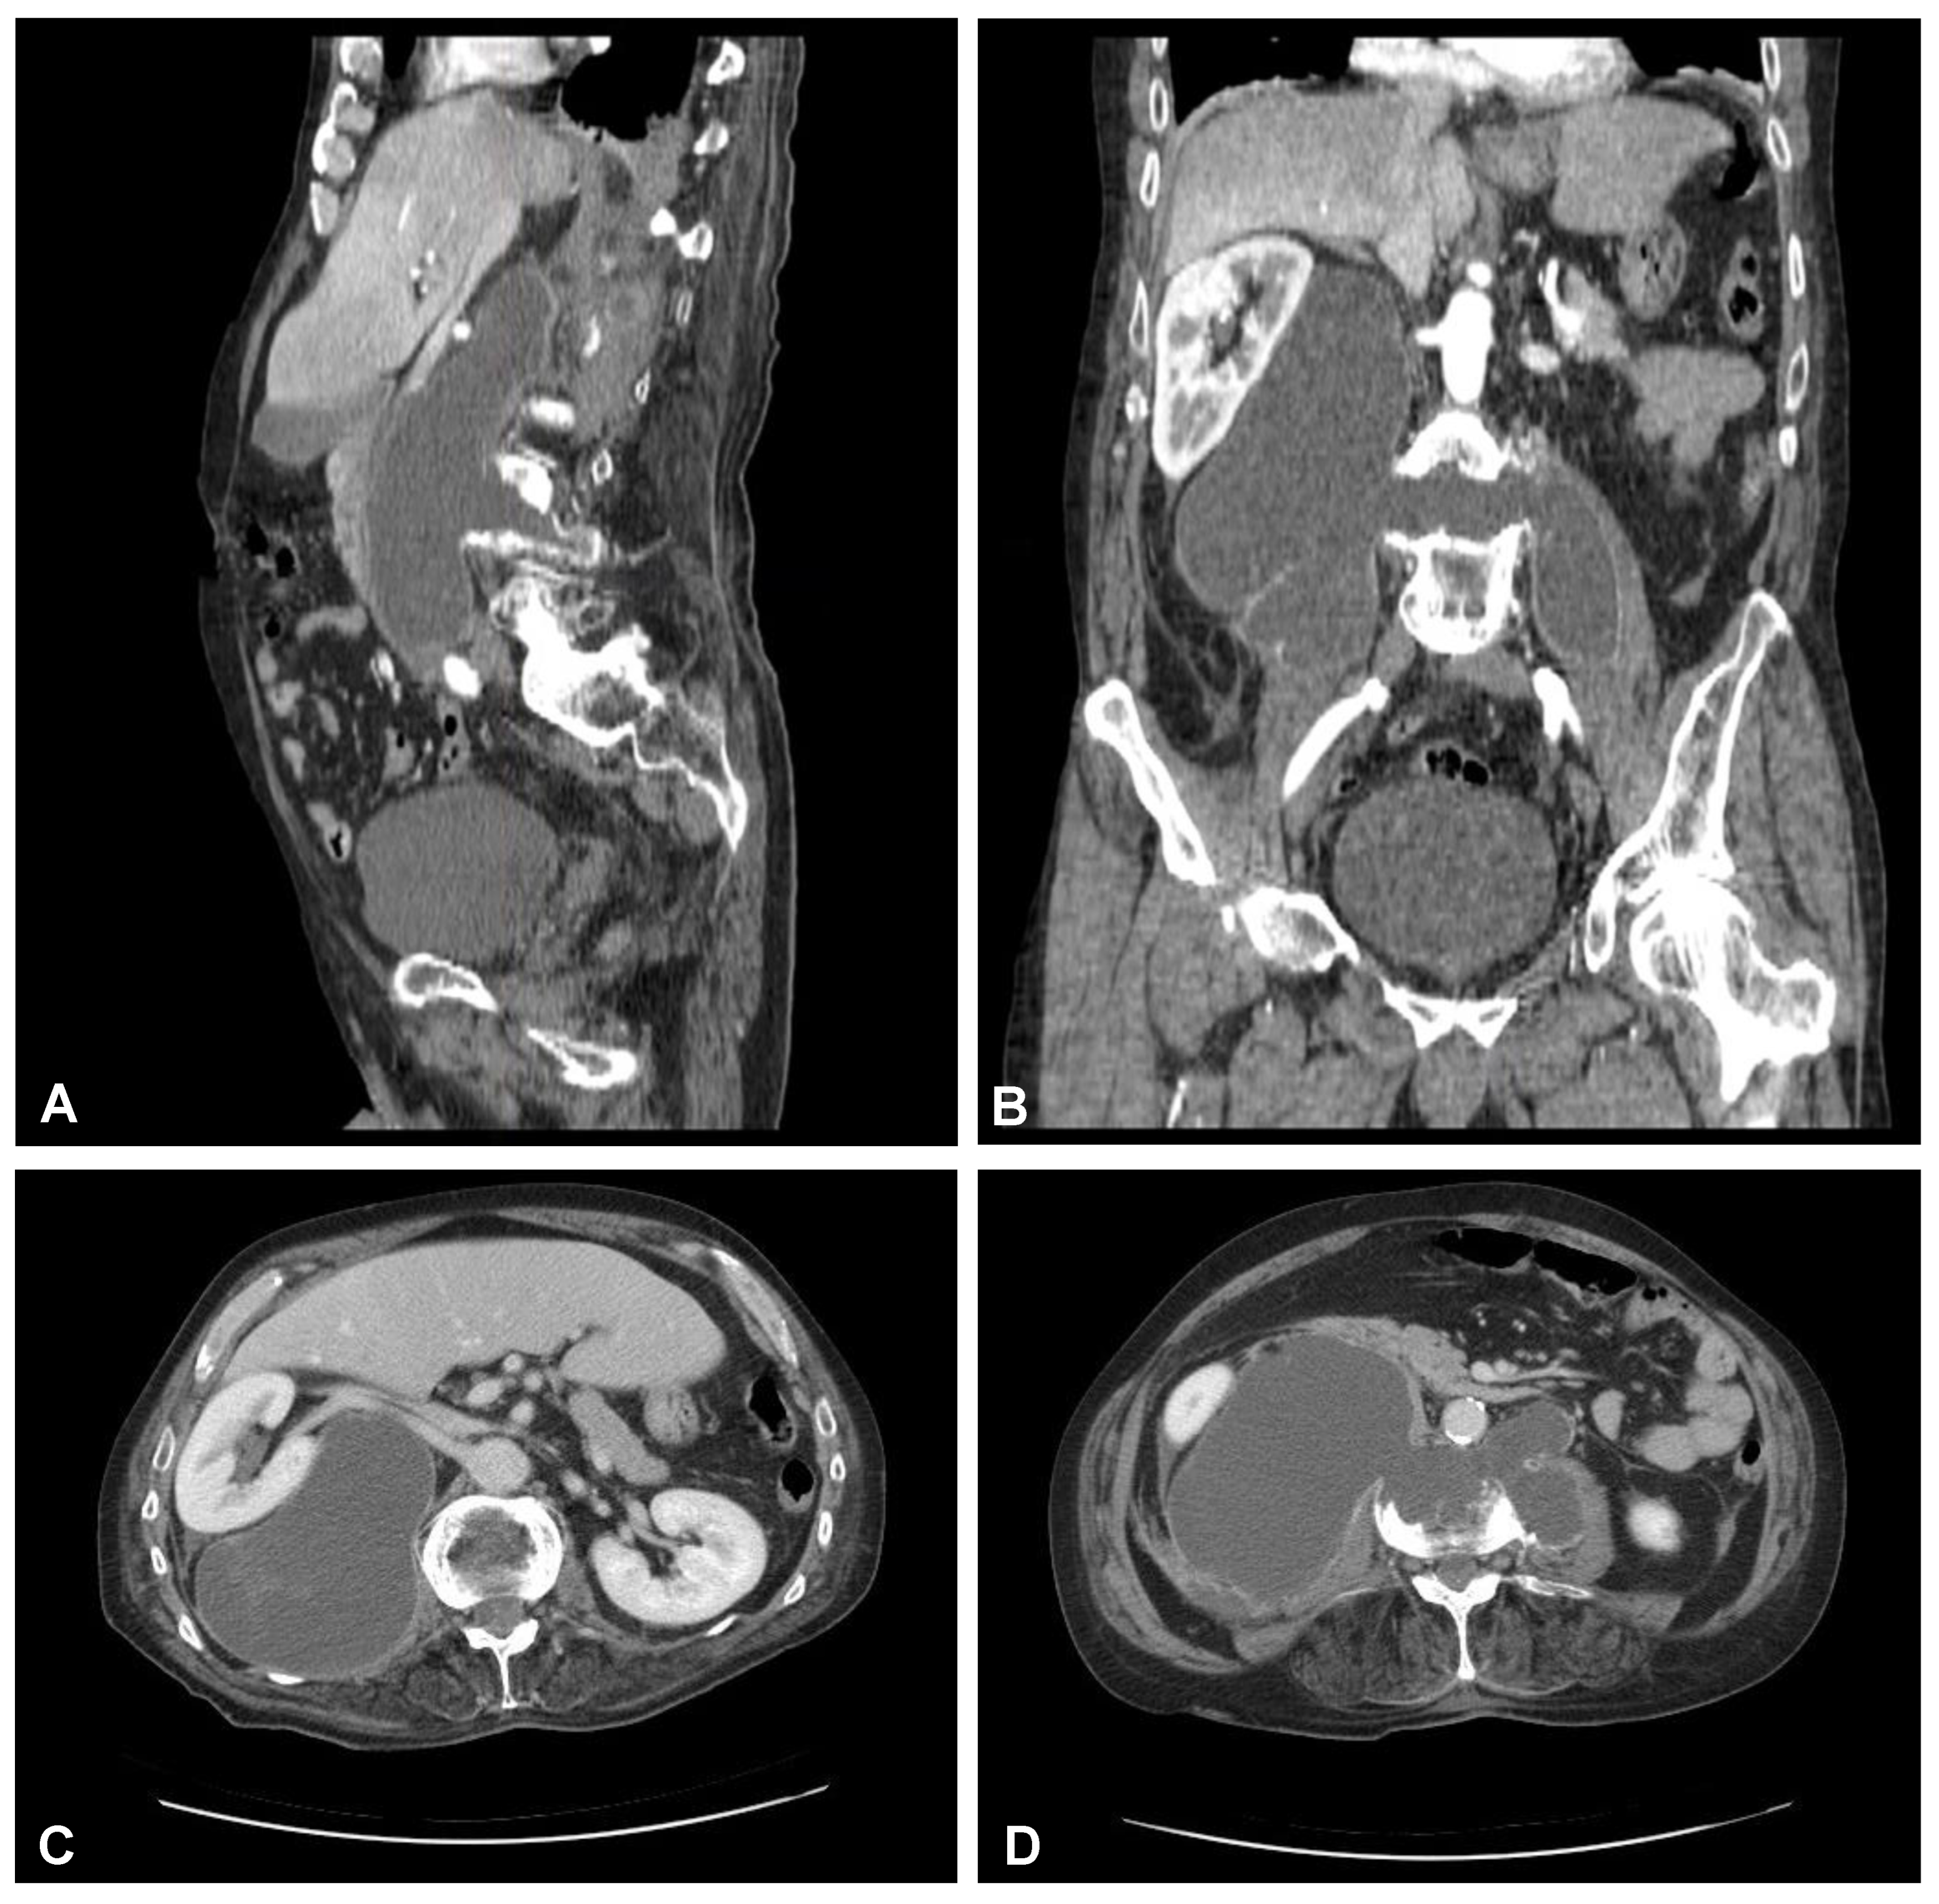

Figure 3. Preoperative sagittal (A), coronal (B), and axial (C,D) CT scans (contrast enhanced) of the lumbar spine demonstrating hypodense area with enhancing wall at the L3/L4 intervertebral disc space communicating with both psoas major muscles forming massive well-defined fluid-like collection in the right retroperitoneum.

A 59-year-old man presented to the hospital with atypical abdominal pain for a few days, three weeks after sustaining a low-energy fall. At the time of admission, the patient had normal upper and lower extremity strength and no pathologic reflexes, as well as no bowel or bladder incontinence. The initial performed plain radiograph of the abdomen demonstrated a fracture line completely slicing through the L3/L4 intervertebral disc space and features of ASH (Figure 1). The additional performed computed tomography (CT) scans demonstrated a three-column fracture of L4 vertebrae with a suspicious transdiscal injury at the L3/L4 level, which was morphologically classified as type B3/C according to the Arbeitsgemeinschaft für Osteosynthesefragen (AO) spine classification. Moreover, at the fracture level, the hypodense area communicating intervertebral disc space with both psoas major muscles forming a massive, well-defined fluid-like collection in the right retroperitoneum was observed (Figure 2). In addition, contrast-enhanced CT (CE-CT) showed a thick enhancing wall and internal septae within an area measuring a total of 10 cm × 20 cm × 10 cm (TR × AP × CC) (Figure 3). Furthermore, the performed magnetic resonance imaging (MRI) scans confirmed the cystic nature of the lesion, which had no specific characteristics and demonstrated intensities that were similar to those of cerebrospinal fluid (CSF) (Figure 4). Taking into consideration the history and radiological features, suspicion of spondylodiscitis with osteomyelitis features and retroperitoneal abscess formation was provided by the radiologist. Blood analysis performed on admission revealed the following results: hemoglobin (Hb): 9.6 g/dL; platelet (PLT): 192 × 109/L; white blood cell (WBC): 9.7 × 109/L; and creatinine (CREA): 0.42 mg/dL. Despite the lack of infection symptoms, the patient was empirically administered intravenous antibiotics, including meropenem (1 g every 8 h) and vanomycin (1 g every 12 h), without waiting for microbiological confirmation.